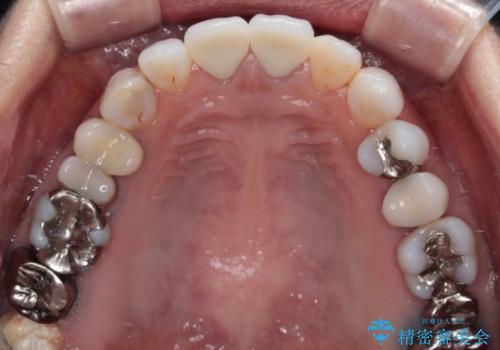

- 変色した保険の前歯のクラウンを交換したいとのことで来院された患者様です。

中心左側の歯はクラウンが装着されており、右側は神経組織が除去されて多少変色している状態でした。

右側の歯も将来的にもっと変色する可能性があるため、前歯2本をオールセラミッククラウンにて補綴治療を行うこととしました。